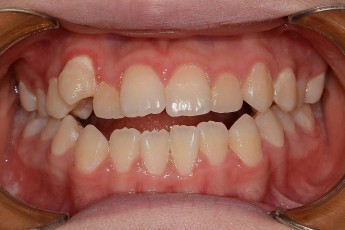

BEFORE & AFTER

- 덧니교정